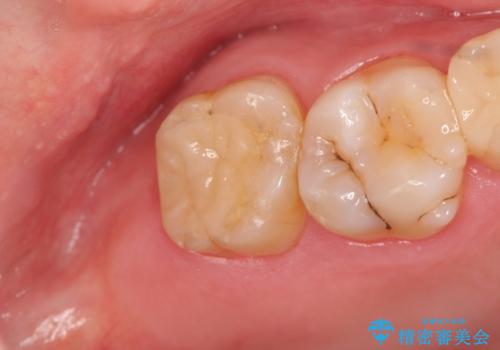

銀歯の劣化・セラミックインレー修復

銀歯辺縁からのセメント漏洩が認められたため、セラミックインレーによる精度の高い修復を行うこととなりました。

劣化の速度が遅い材料を用いて、精度の高い修復を行うことで長期的な予後が期待できます。